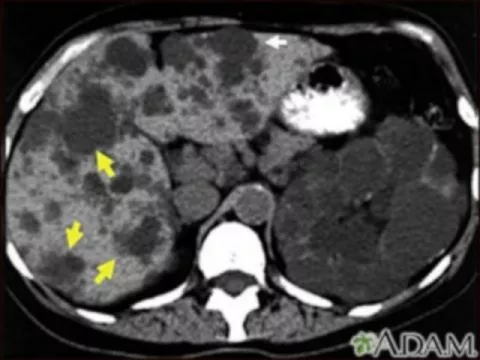

La PQR es una enfermedad o trastorno de los riñones que está causada por un defecto genético hereditario, que se transmite de padres a hijos, la pueden tener algunos hijos y otro no, en la que se forman sacos llenos de agua (quistes) en los riñones, aumentan de tamaño y su tejido funcional disminuye. Tiene 2 formas hereditarias la autosómica dominante y autosómica recesiva.

La 50% de las personas con PQR tienen quistes en el hígado.

- TC abdominal

- Ecografía abdominal